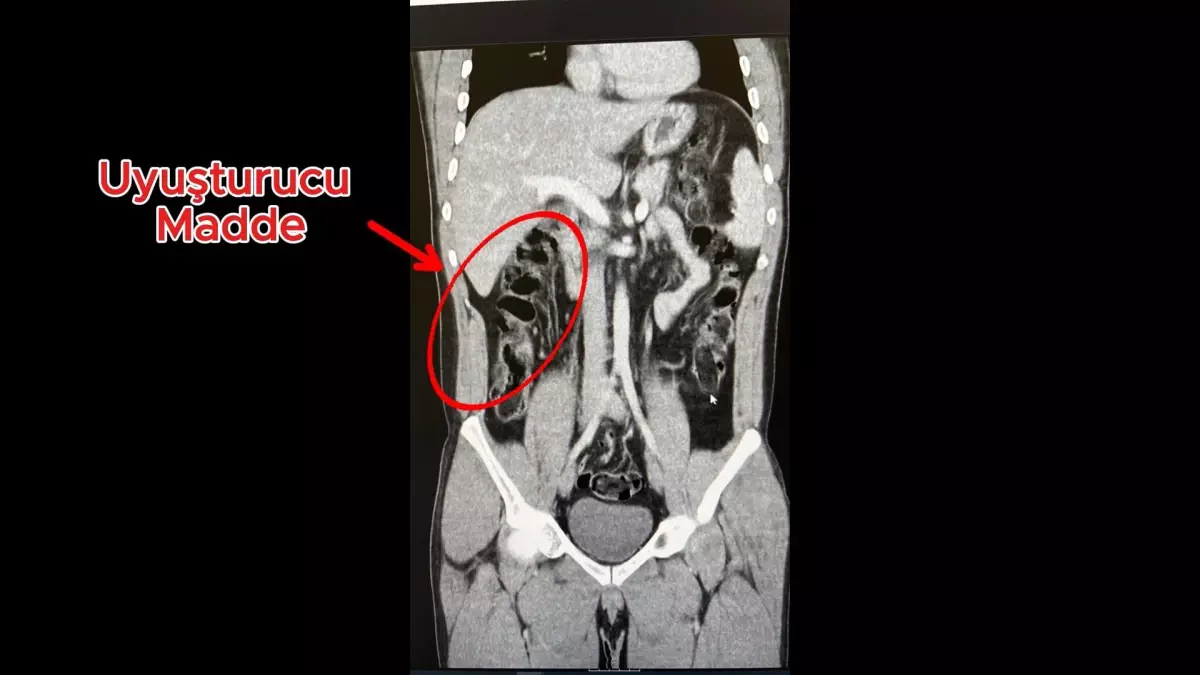

ANTALYA’da uyuşturucu ticareti yapan 2 şüpheli, havalimanında yakalandı. Üzerlerinden uyuşturucu çıkmayan ancak hastanedeki muayenelerinde 35 kapsül eroini yuttuğu belirlenen şüpheliler tutuklandı.

İl Emniyet Müdürlüğü Narkotik Suçlarla Mücadele Şube Müdürlüğü ekipleri, S.S. ve F.M.K. adlı şüphelilerin İran’dan Van’a geçtiğini, yanlarındaki uyuşturucuyu yutarak Antalya’ya geleceğini tespit etti. Şüphelilerin, uyuşturucuyu ‘torbacı’ olarak tabir edilen uyuşturucu satıcıları aracılığıyla piyasaya sürecekleri bilgisi üzerine ekipler, Antalya Havalimanında S.S. ve F.M.K.’yi yakalayıp gözaltına aldı. Aramalarda üzerlerinde uyuşturucuya rastlanmayan 2 şüpheli, iç muayene için hastaneye götürüldü. Hastanedeki iç beden muayenesinde, 2 şüphelinin, toplam 278 gram 35 kapsül halinde eroini yuttuğu saptandı. ‘Uyuşturucu veya uyarıcı madde ticareti yapmak ve sağlamak’ suçundan tutuklanan 2 şüphelinin havalimanındaki görüntüleri, muayene edilme anları ve yuttukları kapsüllerin yer aldığı film sonuçları kameralara yansıdı.